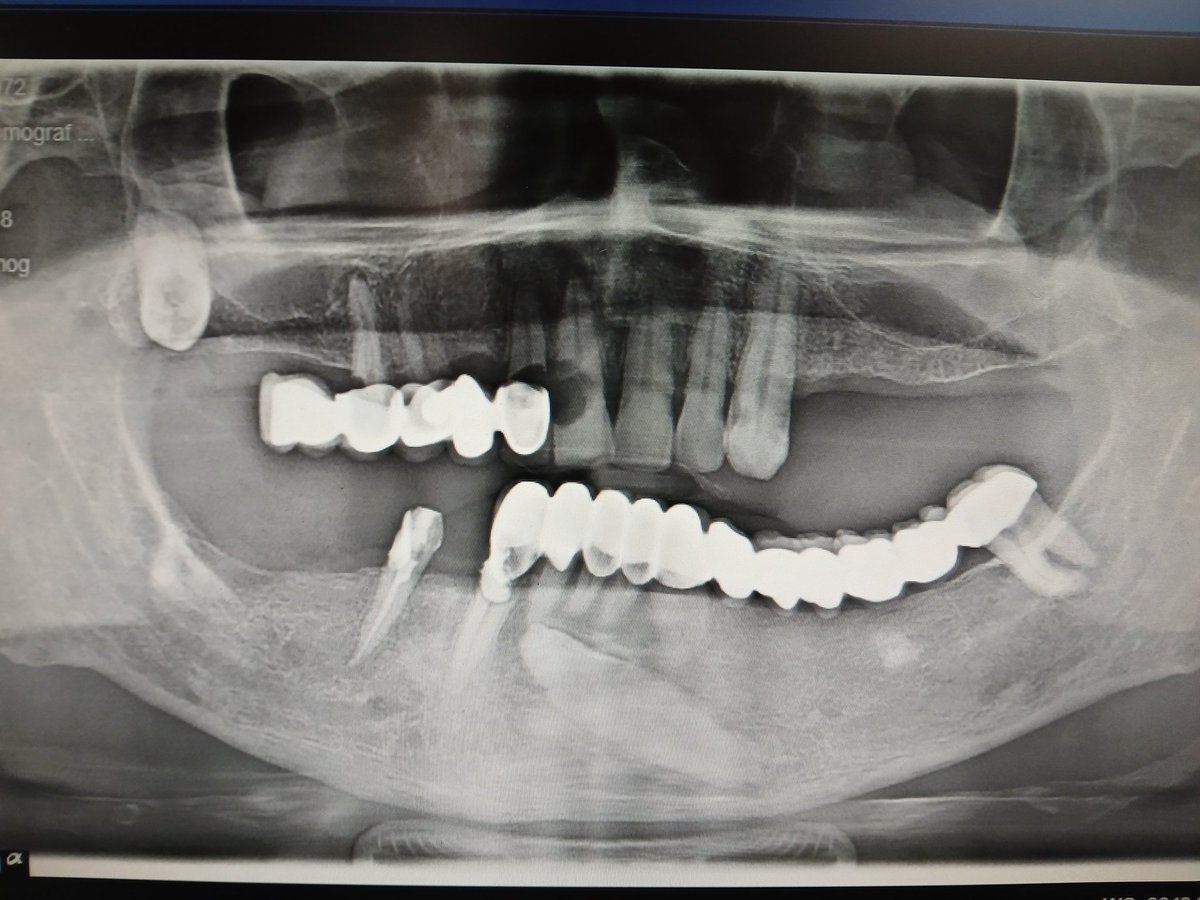

@dent_nasi متاسفانه بگم همکارای نابلد یا شایدم دندانپزشکای تجربی اینکارا رو میکنن و اصلا هم براشون مهم نیست چی میشه الانم خداتومن پول گرفته از این بیچاره

@EhsaT کاری به بریج با موج سینوسیش ندارم.اصلا کاری با دندون اکتوپیفک بالا هم ندارم..وللی اون شئ نامعلوم تو مندیبولا تباهم کرده🤣